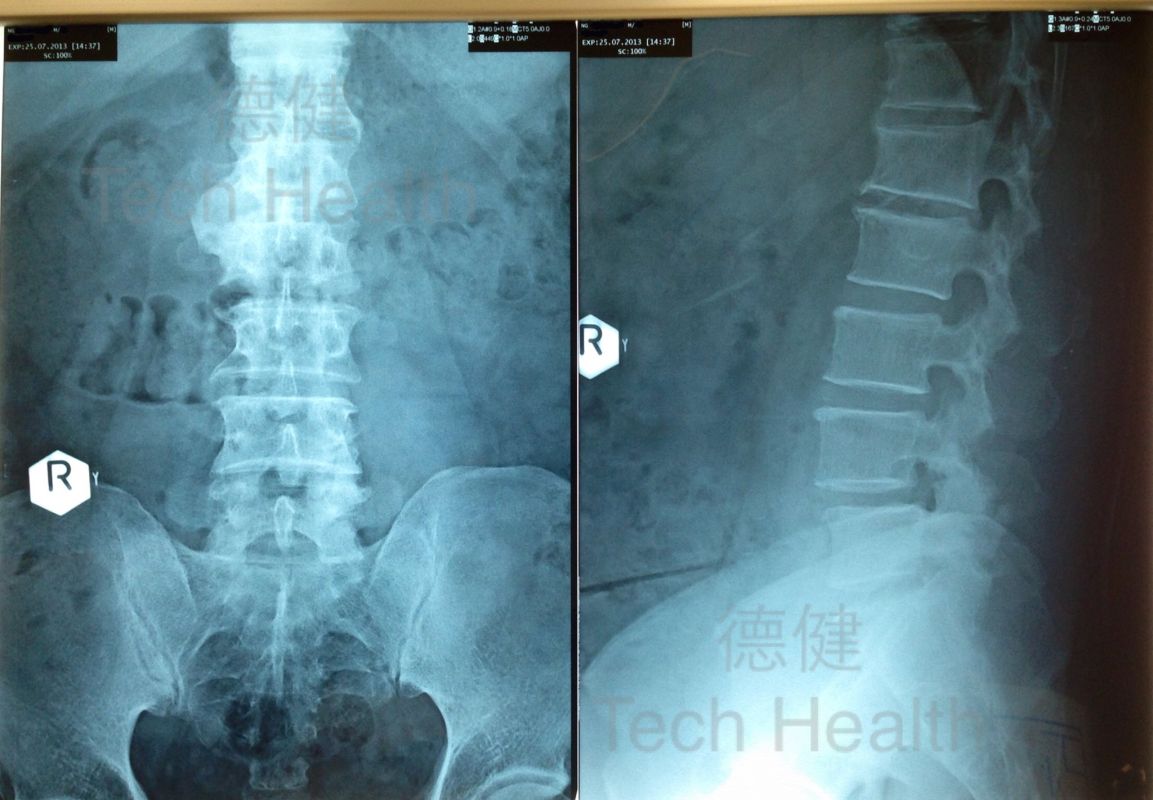

從X光片檢查發現患者頸椎骨痛影響右肩抽痛,腰椎骨L4~L5肌肉及軟組織不正常,神經受壓,引致患者右腰外側疼痛及右腳抽痛,晚間時有抽筋情況出現。- 2013/07/24 初診。患者經過1次經穴激活系統療法的組合治療後,疼痛感覺明顯減輕,當日覺舒服約三小時 。